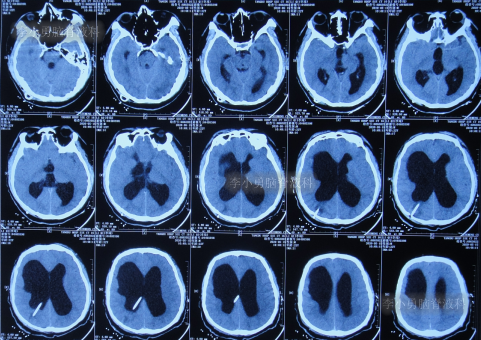

发现脑积水8年后即2013年9月16日,复查头颅CT示脑积水(图-1),没有相关症状,建议定期复查。

图-1:2013年9月16日头颅CT